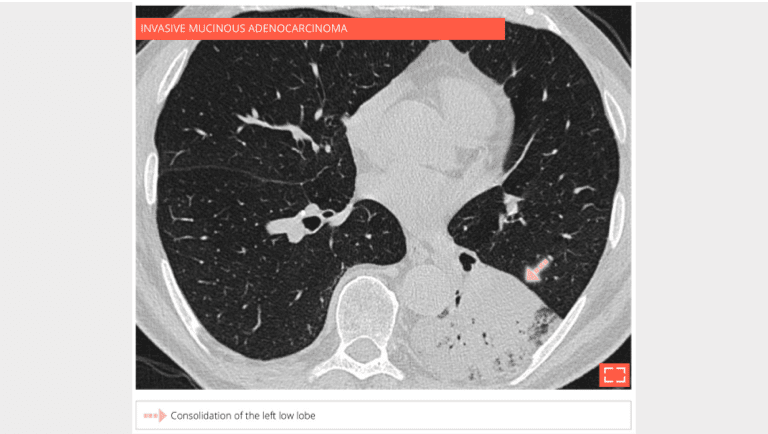

• pneumonic-type mucinous adenocarcinoma

• Chronically evolving pulmonary consolidation (> 8 weeks) that is retractile with air bronchogram.

• The chronic nature of it means a fibroscopy with lavage must be performed.

• If results are negative, a transparietal lung biopsy should be suggested.